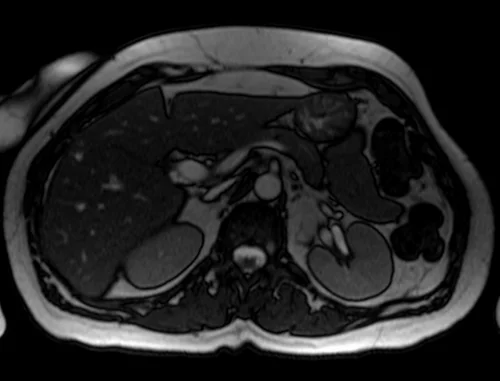

mrcp axial trufi image 3 - MRI